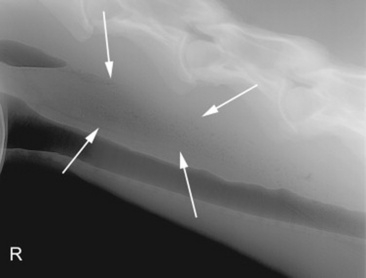

Survey radiography is generally helpful to evaluate the cervical esophagus for evidence of rupture as well as to evaluate the abdomen. Esophageal ruptures secondary to an obstruction or vigorous placement of a nasogastric tube result in a small volume of gas that tracks just dorsal to the trachea (Fig. 32-2). This can be confused with a tracheal laceration; however, with tracheal lacerations generally the gas accumulation will surround the trachea and the volume of gas within the subcutaneous tissues and the cranial mediastinum will be severe. In addition, esophageal obstructions, also called choke, can sometimes be identified on survey radiographs depending on the material that is causing the obstruction and the amount of air or contrast medium that is able to surround the structure (Fig. 32-3). Although the nature of the obstruction cannot be determined, the extent of the abnormality can sometimes be identified.

Fig. 32-2 Standing lateral radiograph of a 13-year-old Morgan gelding with an esophageal tear. Note the tubular region of small gas opacities caused by air trapped around the outer border of the esophagus (arrows). An esophageal perforation secondary to an ingested foreign body was confirmed with endoscopy.